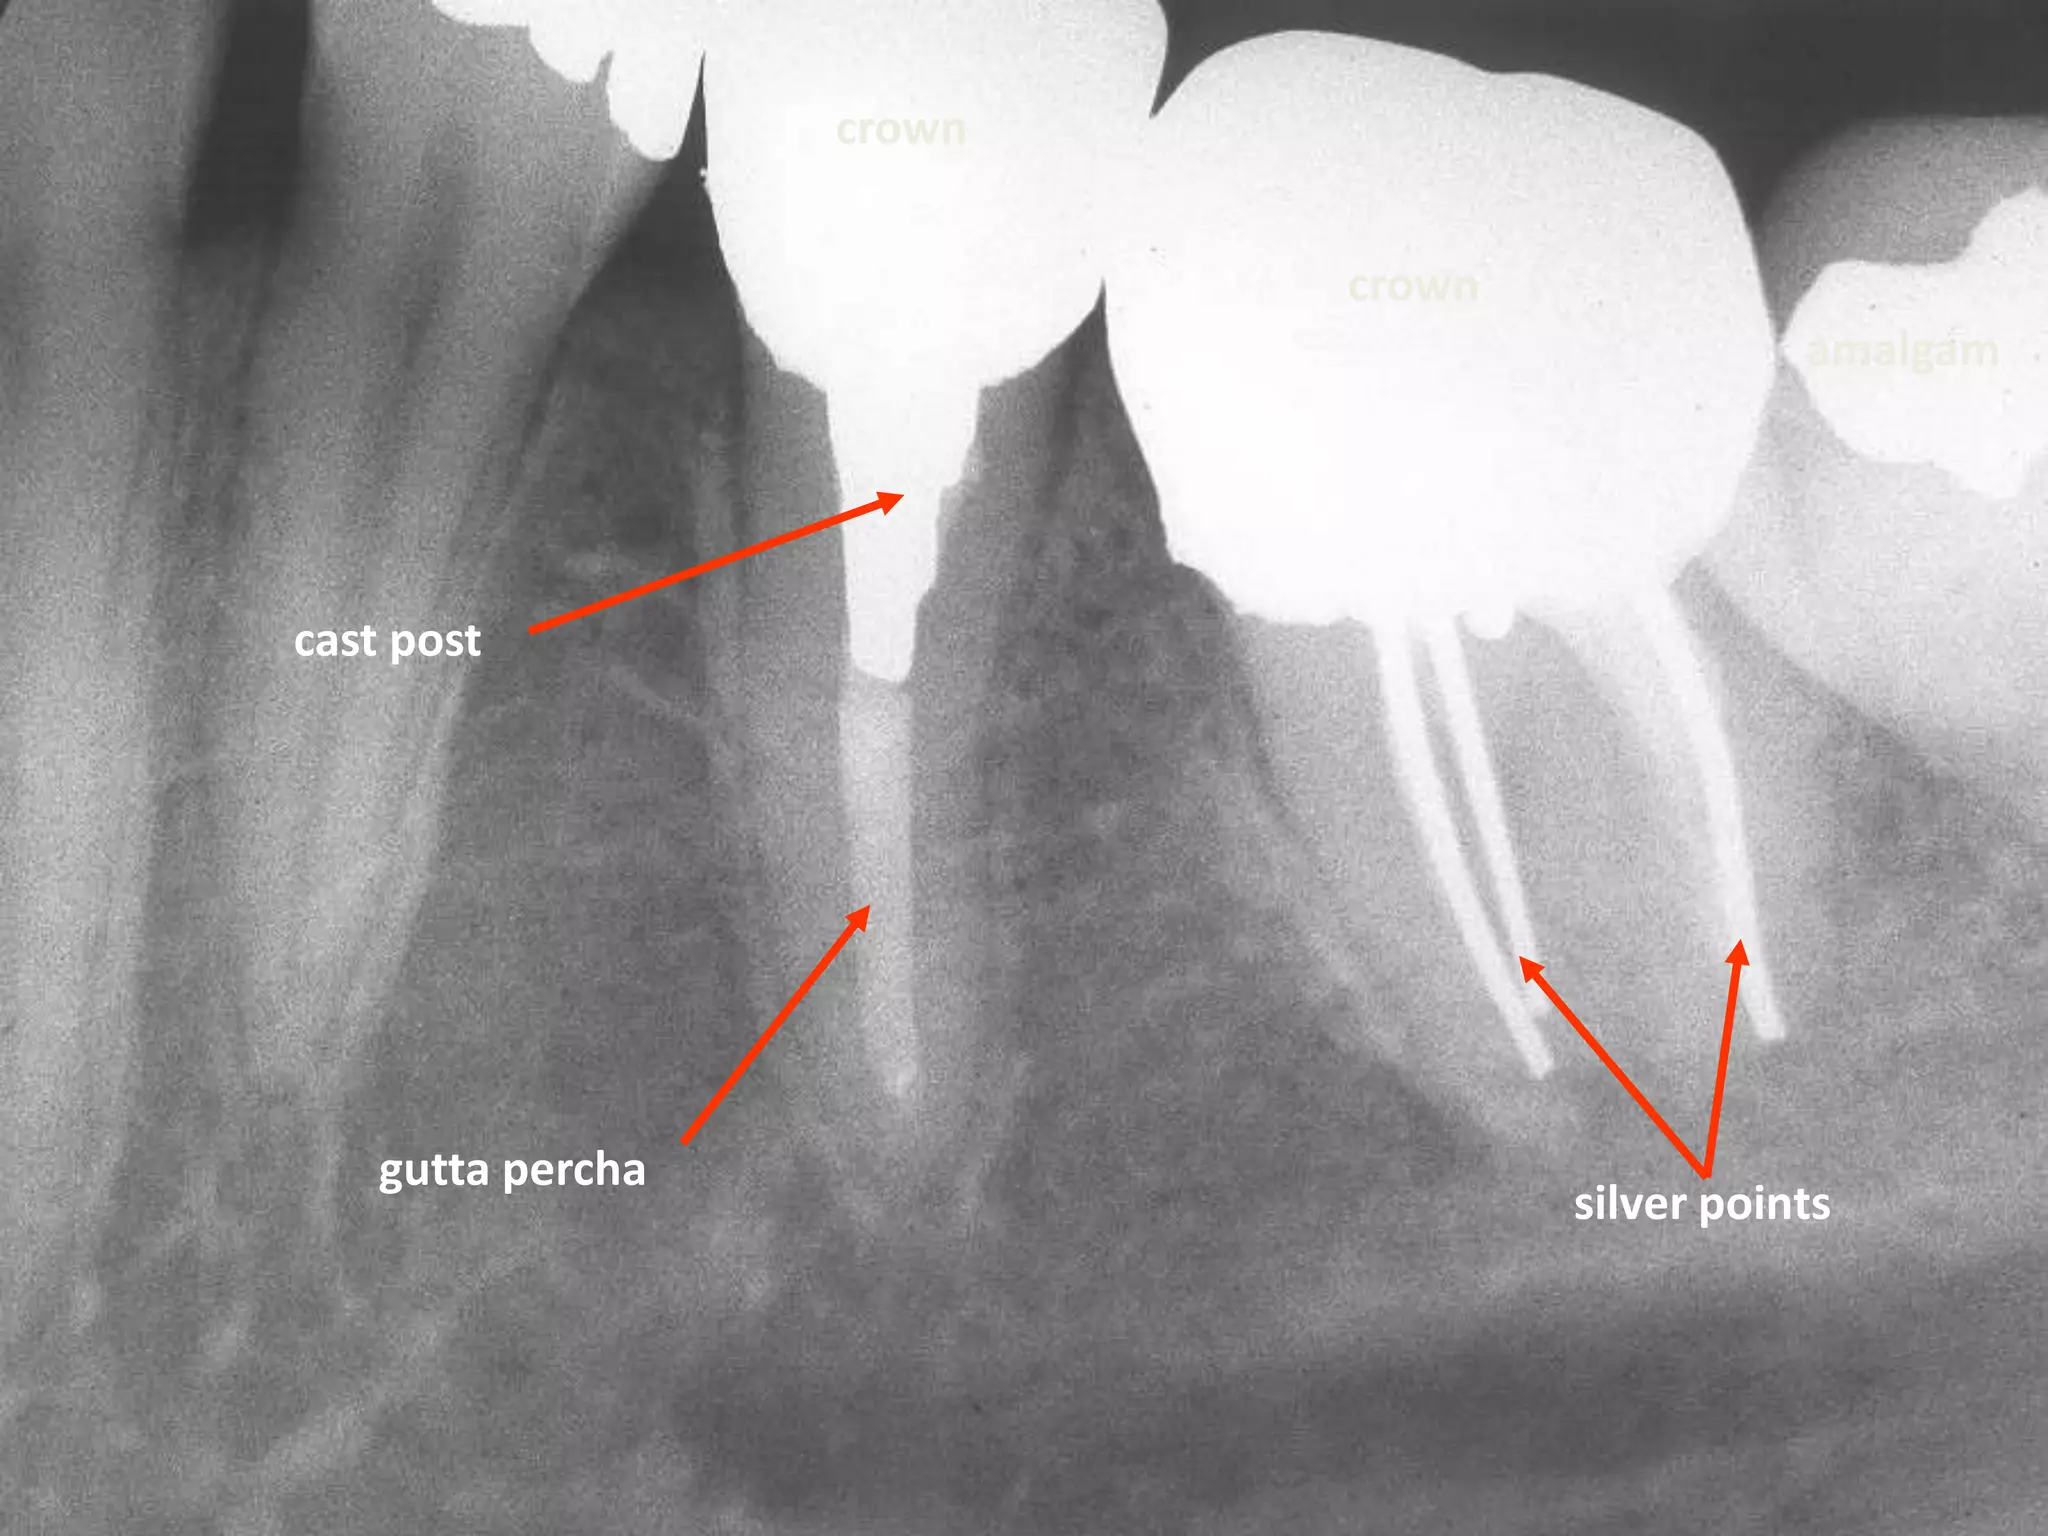

Restorative Materials

Radiopaque: Structures with higher object

density, such as amalgam, gold, silver

points, pins, gutta percha, porcelain.

Gold crowns, amalgams

Retention pins

porcelain

crowns

Ceramic Crowns

crown

amalgam

cast post

gutta percha

silver points